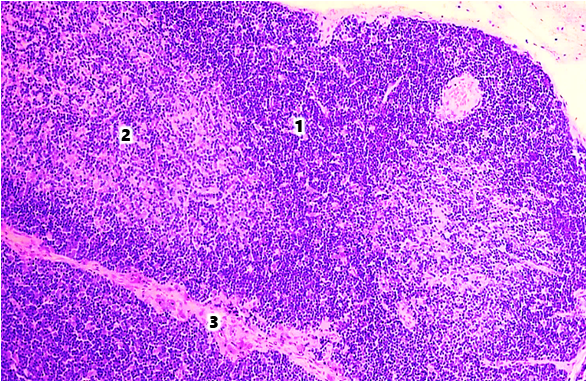

The cortical-cellular index in both age periods was 2.24±0.16% and 1.78±0.36%, respectively. The thickness of the cortex was 248.27±11.54 μm at 6 months of age and 165.27±9.76 μm at 9 months of age.The area of the thymus cortex in white outbred rats in the group with modeled selenium deficiency decreased by 1.05 times at 6 months of age and by 1.07 times at 9 months of age compared to the indicators of intact white rats. It was established that the area of the medullary layer decreased by 5.78% and 6.43%, respectively, in both age periods (Fig. 2). The cortical-cellular index decreased in both age periods and amounted to 2.22±0.12% and 1.76±0.14%, respectively. The thickness of the cortex decreased by 1.06 times at 6 months of age and by 1.07 times at 9 months of age compared to the indicators of healthy white rats. | Figure 2. Thymus of a 6-month-old white rat in the group with alimentary selenium deficiency. Stained with hematoxylin - eosin. Ok. 10 x vol. 10. The area of the 1st cortical layer is reduced, the area of the 2nd medullary layer is increased, the 3rd trabecula is thickened |